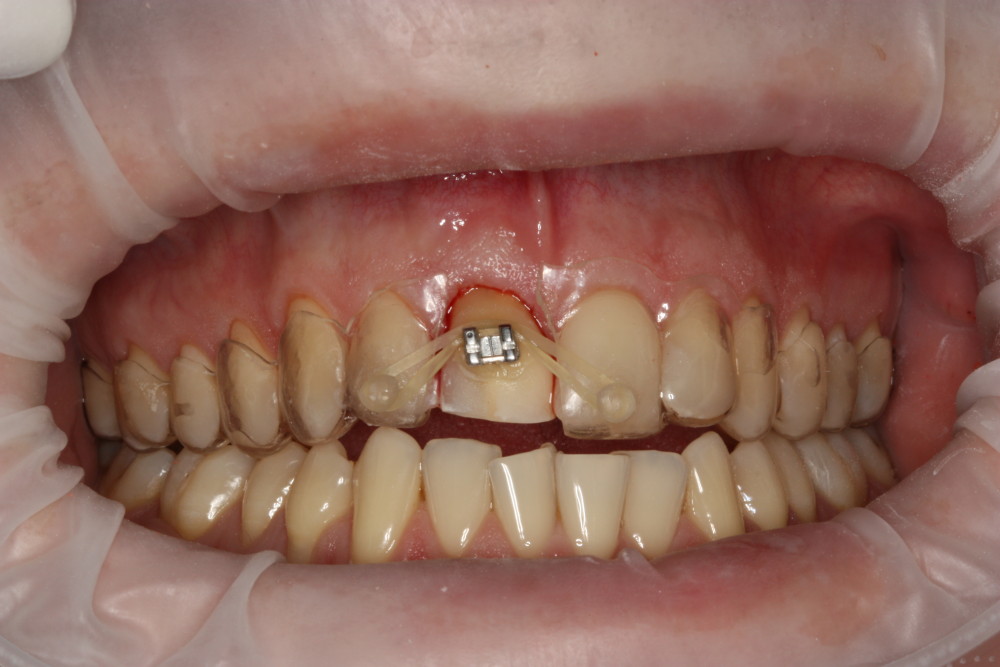

Przykład ekstruzji ortodontycznej za pomocą płytki termoformowalnej i zameczka ortodontycznego: